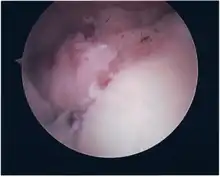

Repair of SLAP tear

- Locations for the bone anchors are selected based on number and severity of tear. A severe tear involving both SLAP and Bankart lesions may require seven anchors. Simple tears may only require one.

- The glenoid is drilled for the anchor implantation.

- Anchors are inserted in the glenoid.